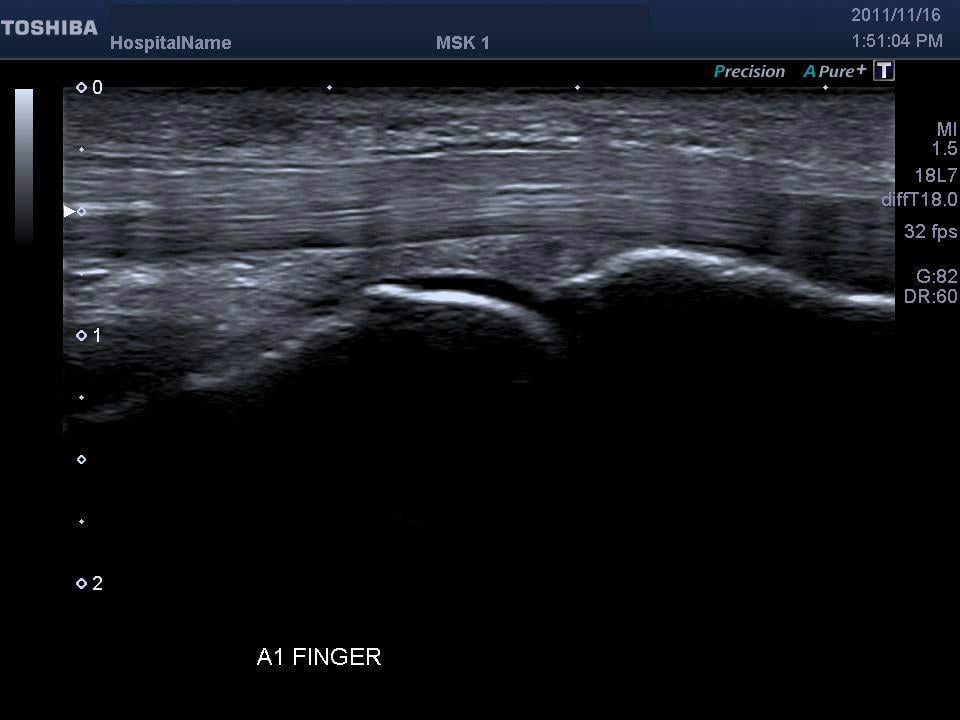

ultrasound of the A1 pulley of the finger together with the flexor A1 Pulley Finger Ultrasound Web ultrasound provides a direct and precise visualization of the thickness, width and location of a1 pulley lesion. Web trigger fingers are a type of stenosing tenosynovitis involving the flexor digitorum superficialis at the level of the a1 pulley. Web trigger finger (trigger thumb when involving the thumb) is the inhibition of smooth tendon gliding due to mechanical impingement at. A1 Pulley Finger Ultrasound.

A1 Pulley Finger Ultrasound . Web trigger finger (trigger thumb when involving the thumb) is the inhibition of smooth tendon gliding due to mechanical impingement at the level. Role is to support and guide the flexor tendons along the bone. Web diagnosis is based on the presence of pain and tenderness of the a1 pulley in grade i green’s classification, 28 catching during flexion and. Web ultrasound provides a direct and precise visualization of the thickness, width and location of a1 pulley lesion. Web trigger fingers are a type of stenosing tenosynovitis involving the flexor digitorum superficialis at the level of the a1 pulley.